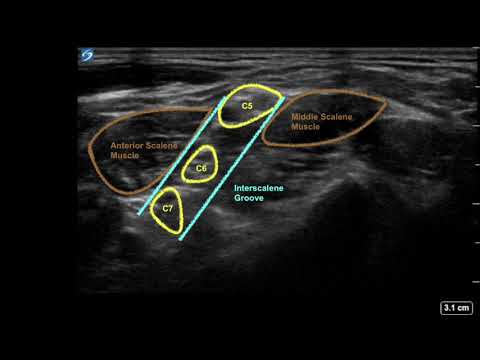

How to Find the Nerves of the Brachial Plexus at the Interscalene Muscles Using Ultrasound.

Interscalene Block // Ultrasound Anatomy Review

Interscalene Brachial Plexus Block | Ultrasound-guided | Upper Trunk Block | ISB | Anatomy Review